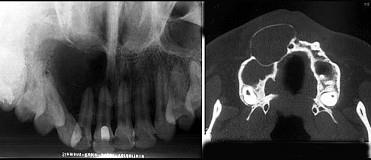

位于上颌侧切牙与尖牙之间的非牙源性囊肿(影像检查如图)是 ( )

A球上颌囊肿

B正中囊肿

C鼻唇囊肿

D鼻腭囊肿

E角化囊肿